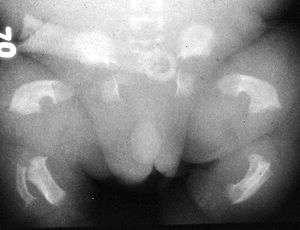

| Radiogram of a baby born with thanatophoric dwarfism | |

Thanatophoric dysplasia (thanatophoric dwarfism) is a severe skeletal disorder characterized by a disproportionately small ribcage, extremely short limbs and folds of extra skin on the arms and legs.

Infants with this condition have disproportionately short arms and legs with extra folds of skin. Other signs of the disorder include a narrow chest, small ribs, underdeveloped lungs, and an enlarged head with a large forehead and prominent, wide-spaced eyes. Thanatophoric dysplasia is a lethal skeletal dysplasia divided into two subtypes. Type I is characterized by extreme rhizomelia, bowed long bones, narrow thorax, a relatively large head, normal trunk length and absent cloverleaf skull. The spine shows platyspondyly, the cranium has a short base, and, frequently, the foramen magnum is decreased in size. The forehead is prominent, and hypertelorism and a saddle nose may be present. Hands and feet are normal, but fingers are short. Type II is characterized by short, straight long bones and cloverleaf skull.[1] It presents with typical telephone handled shaped long bones and a H-shaped vertebrae.

Infants with type 1 thanatophoric dysplasia also have curved thigh bones, flattened bones of the spine (platyspondyly) and shortened thoracic ribs. Note: Prenatal ultra-sound images of the ribs sometimes appear asymmetrical when in fact they are not. In certain cases, this has caused a misdiagnosis of Osteogenisis Imperfecta (OI) type II.